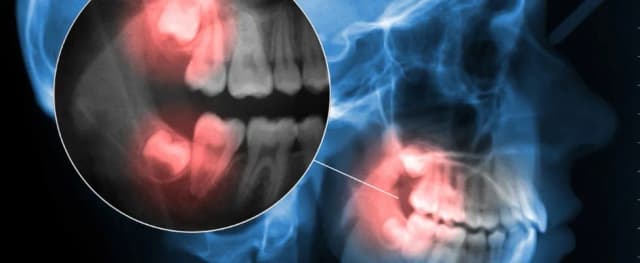

Czy ósemki rosną na górze? Odkryj prawdę o zębach mądrości

Czy ósemki rosną na górze? Dowiedz się, gdzie wyrastają zęby mądrości i jakie problemy mogą się z nimi wiązać. Sprawdź, co warto wiedzieć!